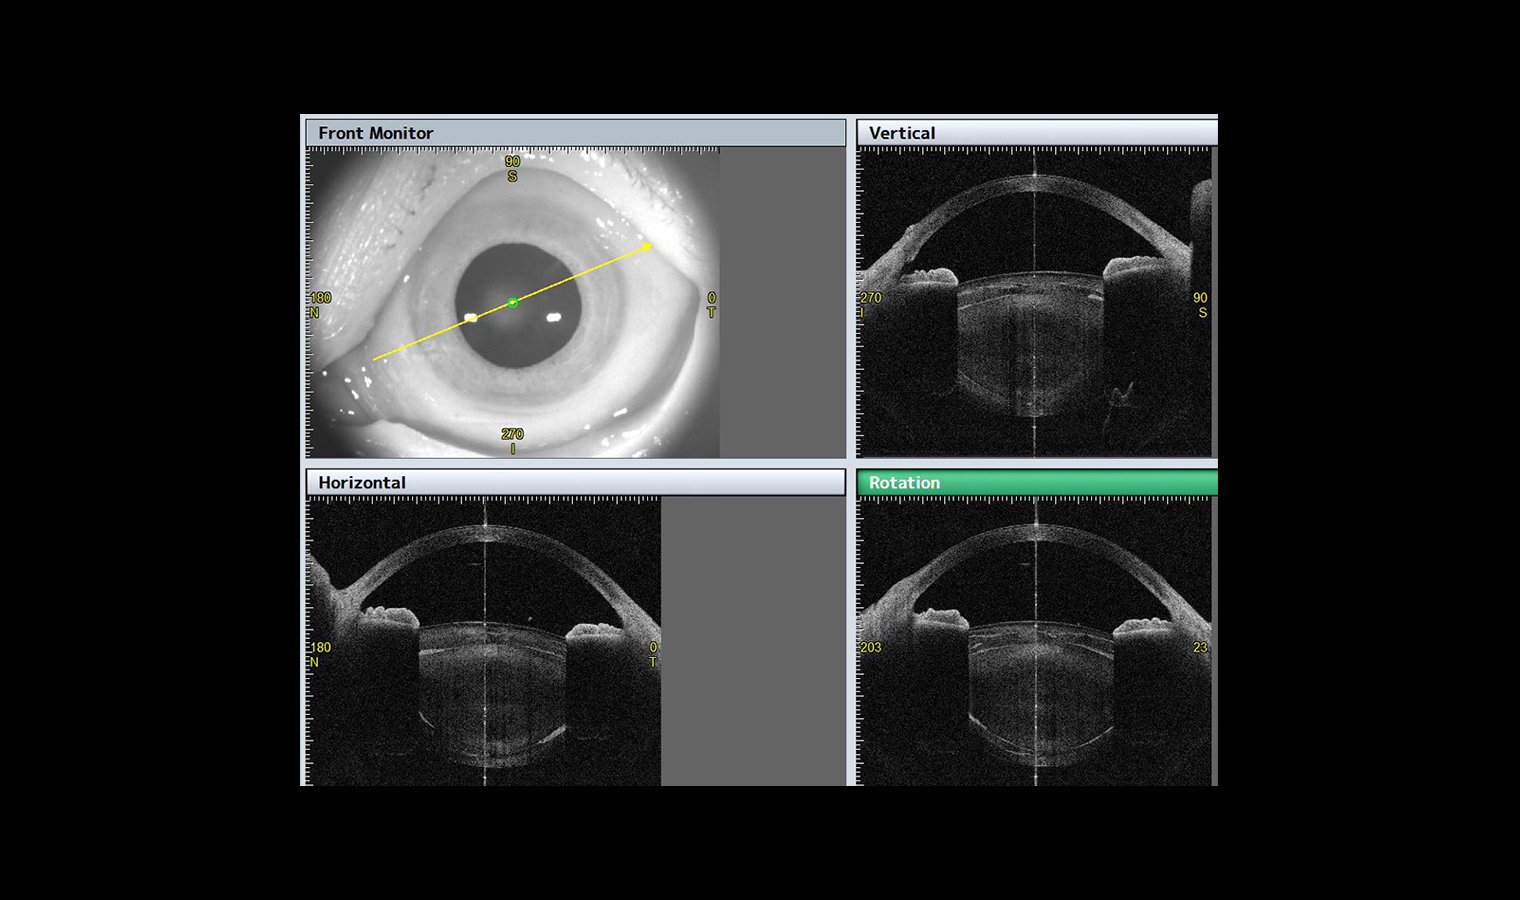

- analiza kształtu soczewki,

- Symulacja fakijnej soczewki wewnątrzgałkowej

W aplikacji STAR 360°, CASIA2, dzięki automatycznemu wykrywaniu ostrogi twardówki mierzy kąt przesaczania na pełnym obwodzie przedniego segmentu, co zapewnia szczegółowe parametry umożliwiające perfekcyjną diagnostykę jaskry.

Nie tylko mierzy, ale także wyświetla wynik na szczegółowym wykresie/mapie graficznej. Wykresy można wybierać spośród wszystkich wartości pomiarowych w zależności od własnych potrzeb.